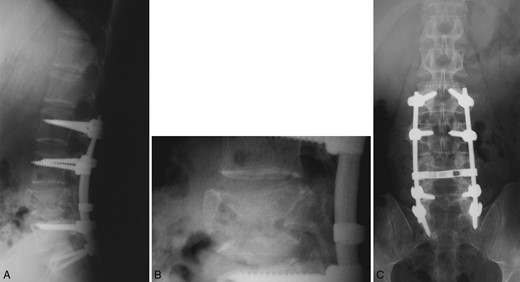

A previously healthy 30-year-old man presented with sudden and intense back pain after lifting a heavy object. Radiological investigation demonstrated an L4 burst fracture with presence of bone fragments in the spinal canal (Fig. 1). Clinical examination was normal except for a mild left foot numbness. His routine laboratory assessment revealed hypochromic microcytic anemia.

Computed tomography scan of the lumbar spine showing an L4 burst fracture.

Treatment with biphosphonates and interferon was initiated, which is well tolerated at 18 months following the diagnosis. Over this period, he has not developed any skeletal or extraskeletal signs of the disease. Regular imaging follow-up did not show any instrumentation failure, new vertebral fracture or subsidence and signs of screw loosening (Fig. 3). Soon after surgery, he returned to his normal activities free of pain without any neurological deficits.

Postoperative plain radiograph of the lumbar spine following L2 to S1 posterior instrumention at 15 months. Good bony fusion is documented at the fractured vertebra with no signs of instrumentation failure.